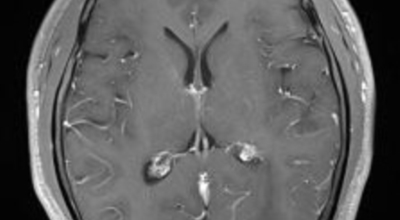

뇌종양이 악성인 경우, 빨리 자라는 특성이 있기 때문에 수술적으로 절제가 필요할 수 있습니다. 하지만 수술로 종양이 완벽하게 제거가 어려운 경우, 수술 후에 방사선 치료와 항암치료를 추가적으로 시행되어요. 요즘 들어서 뇌조직의 훼손을 최소화하고 수술 흉터가 거의 남지 않는 방법으로 하는 치료인 감마나이프 방사선 수술이 있답니다. 이 방사선 수술은 전신 마취와 피부 절개가 필요 없으며, 합병증이나 후유증이 적은 것으로 알려져 있답니다.